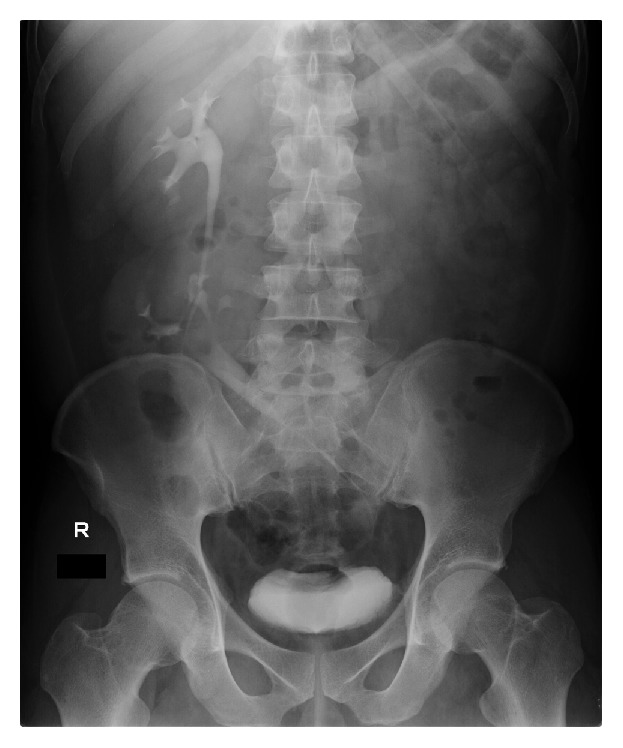

图: 静脉肾盂肾盂造影, 显示出右侧上下融合肾,即左右输尿管。Case Rep Urol. 2016; 2016: 1847213. Published online 2016 Jun 14.

异位肾九成都是和另一侧的肾融合在一块。 男孩较多,通常是左肾跑到右侧, 融合在右肾的下端,上下排列,但输尿管还是在左侧进入膀胱[i]。也有其他融合的“姿势”(L-型,乙状,S 型,盘型,块型等) 。